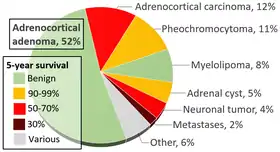

Myelolipomas are rare. They have been reported to be found unexpectedly at autopsy in 0.08% to 0.4% of cases (i.e.: somewhere between 8 per 10,000 and 4 per 1,000 autopsies). They most commonly occur in the adrenal gland, and comprise about 8% of all adrenal tumours.[8] They may also occur in other sites, such as the mediastinum, the liver and the gastrointestinal tract.[1]

- ↑ Data and references for pie chart are located at file description page in Wikimedia Commons.